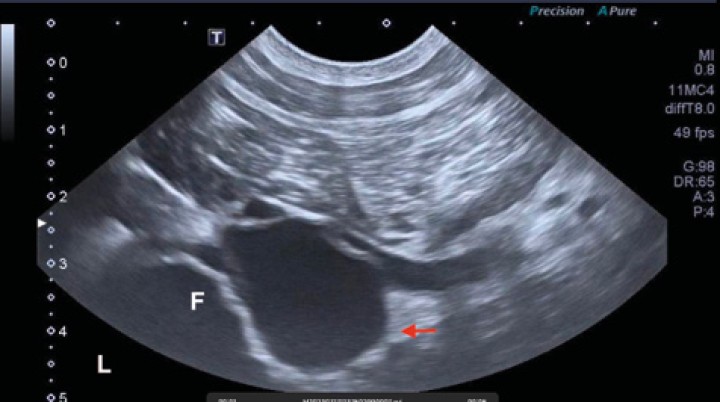

El paciente acudió a visita de control un mes después. Se revisó ecográficamente la lesión vascular de la zona femoral derecha. La estructura aneurismática no presentaba señal Doppler y su contenido no era anecoico, como en el estudio inicial, sino ecogénico (Fig. 7). Los vasos adyacentes a esta lesión eran econormales y con señal Doppler que indicaba permeabilidad. Estos cambios eran compatibles con trombosis en el presunto pseudoaneurisma.

<p>Imagen ecográfica en plano transversal de la región caudodistal del fémur derecho. A la derecha de la imagen se observa una estructura de superficie hiperecoica con sombra acústica que representa la cortical femoral. Se observa una lesión redondeada con contenido ecogénico (flecha roja) que contrasta con el contenido hipoecoico de la vena femoral adyacente. Este hallazgo es compatible con trombosis de la estructura aneurismática visualizada en estudios anteriores. Estudio realizado 1 mes después de la primera ecografía. “M”: medial; “F”: fémur.</p>

Figura 7

Imagen ecográfica en plano transversal de la región caudodistal del fémur derecho. A la derecha de la imagen se observa una estructura de superficie hiperecoica con sombra acústica que representa la cortical femoral. Se observa una lesión redondeada con contenido ecogénico (flecha roja) que contrasta con el contenido hipoecoico de la vena femoral adyacente. Este hallazgo es compatible con trombosis de la estructura aneurismática visualizada en estudios anteriores. Estudio realizado 1 mes después de la primera ecografía. “M”: medial; “F”: fémur.